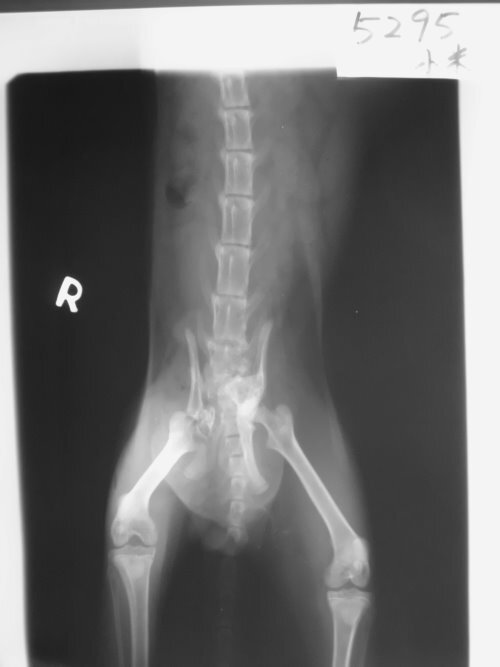

主題: 跛腳的貓咪 申請者姓名: 黃雅卉 花色: 申請日期: 2013-05-10 23:14:47 申請者部落格: 申請者臉書網址: 所在縣市/合作醫院: 高雄市/樂生動物醫院 治療費用: 24900元 需求人數: 26人 已結案 (2013-06-27 14:36:01) 報名人員: 胖姨 x26(已付款)、 候補人員: 動物病情說明: 在三民區灣愛里發現一隻貓咪走路跛腳,似行動有問題的貓咪,立即送醫經醫生診療,發現貓咪體內有許多排泄物,無法自行排出,X光檢查發現骨盆腔及腳骨折,骨盆變形壓迫導致排便困難,第一次緊急手術將腸切開把糞便取出,先解決積便可能會導致的巨結腸,術後貓咪狀況良好,先帶回中途照顧,每天餵食軟便劑和專用飼料,一個月後進行骨盆復位手術,因本人是學生無法支出這筆醫療費用懇求協會求助,請大家幫幫忙貓咪的兩次手術費用。謝謝!